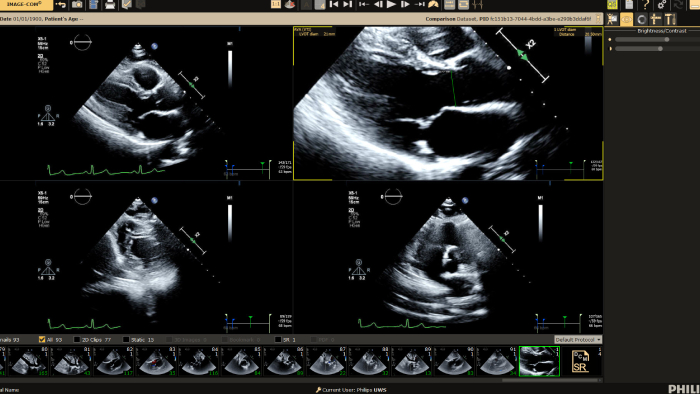

We thank all who were able to attend this year’s European Society of Cardiology programs, including the hands-on workshop sessions, expert symposium on innovations in cardiac imaging workflow, and a friendly open echo skills competition using LifeTec’s Cardiac BioSimulator, the new Philips Compact Ultrasound 5500CV system and Philips Collaboration Live tele-ultrasound.

You can still access recordings of 4 full days of hands-on workshops about best practices in multimodality cardiac imaging with expert teams. See first-time-right imaging for cardiac care, including valvular and related diseases, cardiomyopathies, and intracardiac masses and cardiac tumors.

• Philips helps deliver diagnostic confidence in echocardiography with Ultrasound Compact 5500CV at ASE 2023

Philips helps deliver diagnostic confidence in echocardiography with Ultrasound Compact 5500CV at ASE 2023